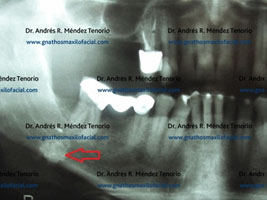

Imágenes de la lesión, caracterizada por tejido mineralizado en el conducto de la glándula submandibular

Condición resuelta una vez que se retira quirúrgicamente el sialolito

Imágenes de control confirmando la eliminación completa de la lesión